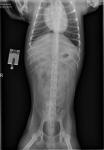

Примерно в 6 месяцев (с декабря 2017 года) у собаки начались припадки похожие на эпилептические (пены нет, глаза открыты, на происходящее вокруг реагирует не всегда). Припадки с каждым разом становятся все более страшными, сперва это были короткие припадки длящиеся 10-15 минут, предпоследний припадок (в сентябре 2019г) длился около 3 часов, собака от боли прикусила язык (было немного крови), а последний припадок длился почти сутки с перерывами произошел он 17.11.2019г. и начался в 8 утра, первый приступ длился около 3 часов (где-то до 11) во время приступа собака очень сильно искусала себе язык было очень много крови. После чего с перерывом в 2 часа было еще около 5 приступов, последний закончился в районе 5 утра следующего дня. Сами приступы по описаниям в интернете можно отнести к клоническим. Сперва собаку начинает сильно трясти, она шатается, еле держится на ногах, после чего происходит спазм, собака падает, происходит судорога всех конечностей и она начинает корчиться от боли - это состояние длится 2-3, иногда и больше минут. После чего происходит расслабление она лежит тяжело дышит и далее все по новой на протяжении нескольких часов. В данный момент у нас на руках есть полный анализ крови, заключение узи брюшной полости, снимок рентген в 2х проекциях и эхокг. Частота припадков иногда меняется, т.е. иногда бывает сильный раз в месяц (на 2-3 часа) а иногда в течение месяца раз в неделю короткие по 30-60 минут. Но припадки случаются не реже 1 раза в месяц. Видео можно посмотреть здесь - https://vk.com/club136053794?w=wall-136053794_11360%2Fall